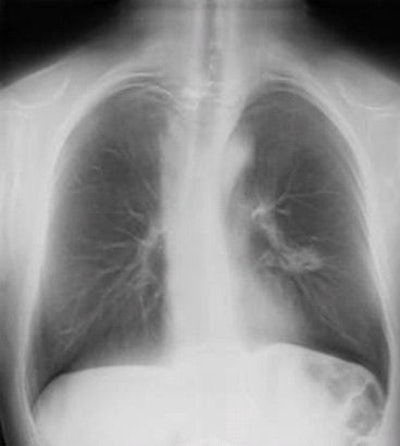

With all the attention being paid to CT lung cancer screening, what about x-ray? Italian researchers believe that radiology's oldest modality could be revived as a screening tool with a technological twist -- digital tomosynthesis. They describe their findings in the June edition of the Journal of Thoracic Oncology.

The utility of x-ray as a lung cancer screening tool has largely been dismissed in several clinical studies, including the 2009 National Lung Screening Trial (NLST), which found that CT had a 20% mortality benefit over screening performed with conventional x-ray.

But digital chest tomosynthesis has the potential to perform better, and it is much cheaper than CT. A group of researchers tested the hypothesis that a population of high-risk former smokers could be screened with tomosynthesis, with suspicious cases sent on to low-dose CT for further workup.

Digital chest tomosynthesis uses an upgraded DR system with a panning tube head. Image courtesy of Dr. Luca Bertolaccini."Although it lacks the depth resolution of CT, tomosynthesis provides some of the benefits of CT at lower costs and radiation dosages," wrote lead author Dr. Alberto Terzi, of S. Croce City Hospital in Cuneo, and colleagues. "Furthermore, digital chest tomosynthesis is less expensive than CT at approximately one-sixths of the cost of a CT" (JTO, June 2013, Vol. 8:6, pp. 685-692).